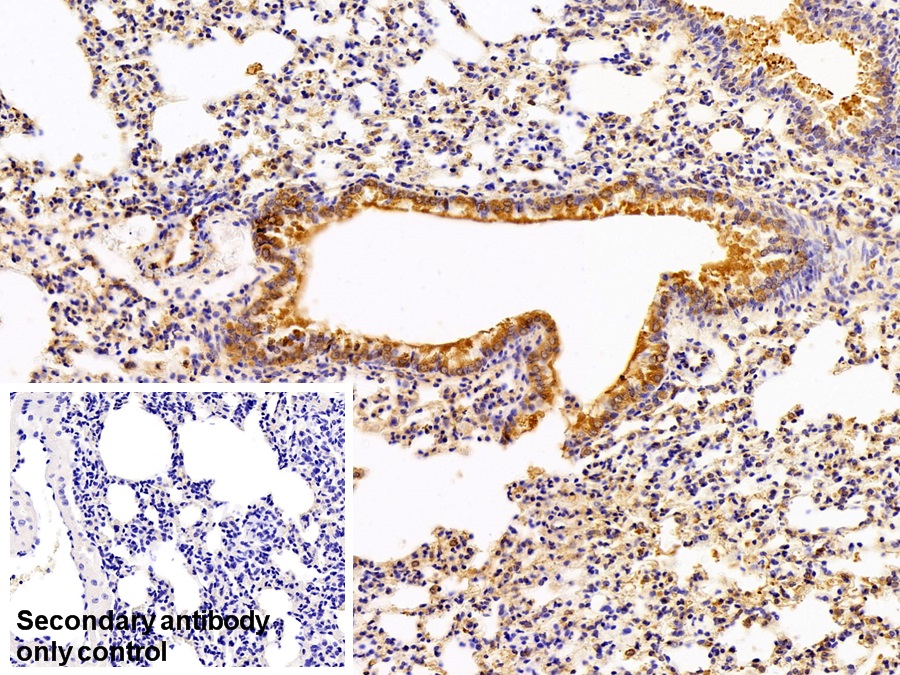

Использование высококачественных первичных антител является неотъемлемым условием получения точных и воспроизводимых результатов в современных научных исследованиях. Например, в рамках онкологического исследования удалось достоверно идентифицировать экспрессию белка PD-L1, что сыграло ключевую роль в оценке потенциальной эффективности иммунотерапии. Применение надежных антител обеспечило стабильность сигнала и высокую специфичность детекции, что позволило получить данные, пригодные для публикации в рецензируемых научных изданиях.

Способы применения первичных антител

Первичные антитела используют в разных методах: от вестерн-блоттинга до иммунофлюоресценции и проточной цитометрии. Всё решает подготовка: нужно грамотно выбрать буфер, точно рассчитать, сколько продукта добавить, и не затянуть с инкубацией. Например, в вестерн-блоттинге без правильной блокировки мембраны фон может всё испортить, а в иммунофлюоресценции фиксация клеток решает, будет ли сигнал ярким. Мы не просто продаём реагенты, а помогаем довести эксперимент до результата: подбираем реагенты и даём советы по методам, если есть специфика в протоколах производителя. Нужен особый подход? Оформите спецзаказ по ссылке — мы найдём решение для вашего проекта.